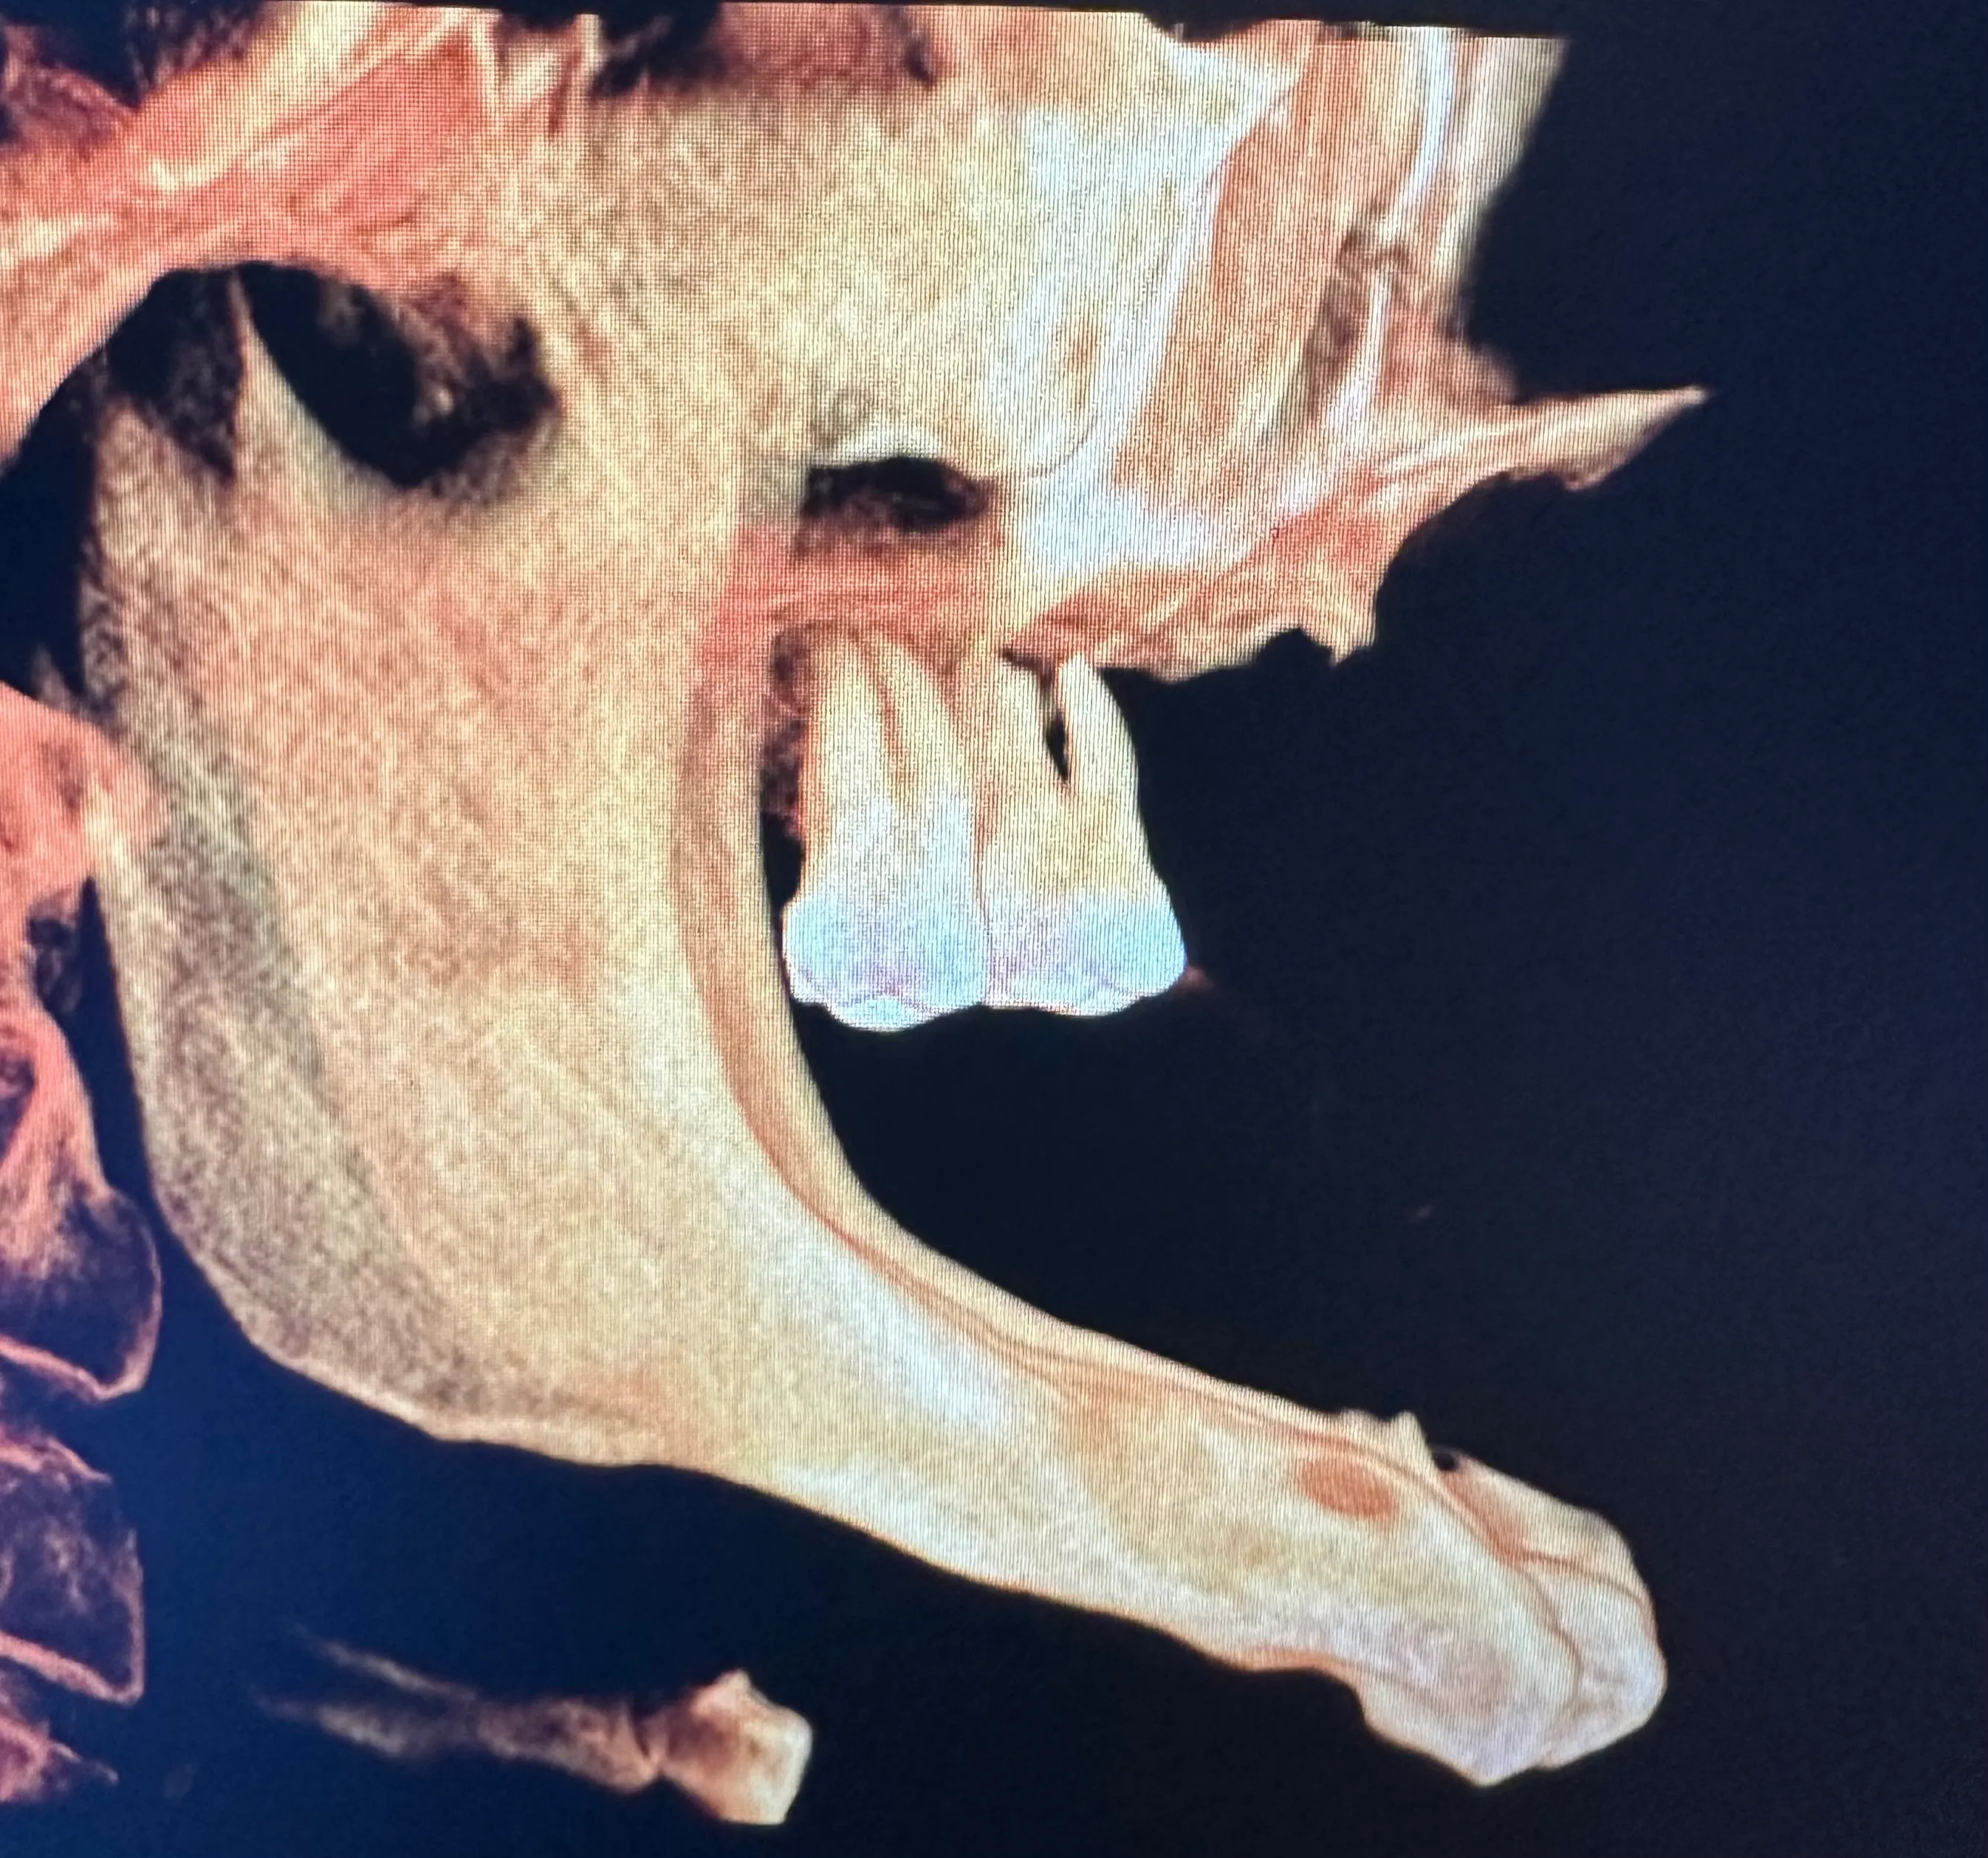

Some patients need only one or two dental implants, while others are completely edentulous (missing all teeth). As with other well-known implant-supported denture options, zygoma implants can support a full arch of prosthetic teeth on just four screws without bone grafting.

Normally, implants are placed in the maxilla to replace missing teeth in the upper jaw. However, some patients have such severe bone loss that there isn’t enough to place an implant safely. In this case, longer implant screws can be used to reach the cheekbones, which are used as an anchor instead.

Zygomatic dental implants are sometimes called “rescue implants” because they can help patients achieve a fully functional bite and aesthetically pleasing smile when bone grafting isn’t possible.

Without regular stimulation from chewing and biting, jawbone loss (resorption) occurs. We frequently see significant bone loss in patients who have been using dentures for many years. Unfortunately, patients with maxilla resorption are often told that there is no hope for bone grafting or dental implants. However, this is not always the case.